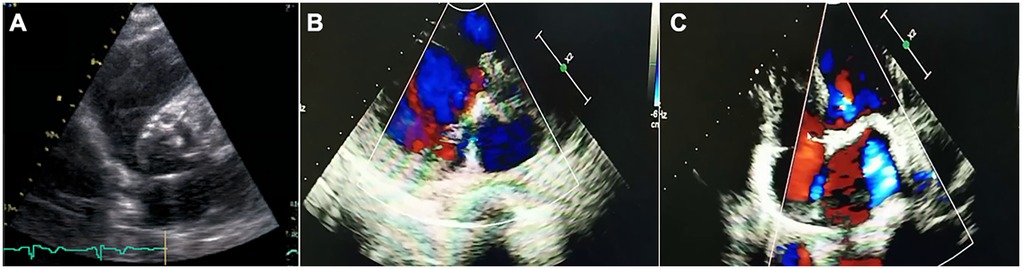

Figure 2

Transthoracic echocardiographic assessment of aortic stenosis in the proband. (A) Parasternal short-axis view showing tricuspid aortic valve with markedly thickened, calcified leaflets (arrows) and restricted systolic opening. (B,C) Apical five-chamber views with color Doppler demonstrating high-velocity, turbulent systolic flow (mosaic pattern) across the stenotic valve, consistent with severe obstruction.

He was diagnosed with severe aortic valve calcification and stenosis at age 39 during an investigation of his symptoms. A comprehensive cardiac assessment confirmed complex valvular heart disease. Transthoracic echocardiography showed a severely stenotic aortic valve, noted to be morphologically tricuspid but with extensive calcification, leaflet thickening, and commissural fusion restricting opening (Figure 2A). Color Doppler interrogation revealed high-velocity, turbulent flow consistent with severe stenosis (peak gradient > 80 mmHg, mean gradient > 50 mmHg, calculated valve area < 0.8 cm²), accompanied by moderate mitral stenosis with regurgitation, moderate tricuspid regurgitation, and markedly elevated estimated systolic pulmonary artery pressure (84 mmHg) (Figures 2B,C). Standard laboratory investigations, including complete blood count, inflammatory markers (CRP, ESR), renal and hepatic function panels, fasting glucose, HbA1c, and serum phosphocreatine kinase, were unremarkable. Chest radiography demonstrated cardiomegaly and a distinct pyriform (pear-shaped) thoracic configuration. Cardiac computed tomography (CT) provided detailed anatomical information, confirming massive calcification involving the aortic valve leaflets, aortic annulus, and mitral valve annulus, and extending into the left ventricular outflow tract (Figures 1D,E).

Evaluation for common etiologies of premature valvular stenosis was undertaken. The patient had no history or evidence of hypertension, diabetes mellitus, or hyperlipidemia; his lipid profile was within normal limits. Electrocardiogram showed left ventricular hypertrophy but no significant conduction abnormalities and coronary CT angiography excluded obstructive coronary artery disease. The tricuspid morphology identified on both echocardiography (Figure 2A) and CT effectively ruled out bicuspid aortic valve disease, a common cause of stenosis in younger adults. Furthermore, serum calcium, phosphate, parathyroid hormone (PTH), and 25-hydroxyvitamin D levels were all within the normal physiological range, making primary disorders of calcium homeostasis an unlikely explanation for the extensive calcification.

The diagnostic workup in the proband systematically excluded more common causes of severe aortic stenosis in a relatively young adult. The congenital bicuspid aortic valve was ruled out based on clear tricuspid morphology on imaging (Figure 2A). Standard atherosclerotic risk factors were absent, and coronary arteries were free of significant disease. Rheumatic heart disease was unlikely given the valvular morphology and lack of supporting history. Furthermore, normal calcium and phosphate metabolism excluded systemic mineral balance disorders as the primary driver of extensive valvular calcification (14, 15). The co-segregation of the homozygous p.Glu262Gly LMNA mutation with the MADA phenotype and severe cardiac valvular disease in both affected siblings, born from consanguineous parents who are heterozygous carriers, strongly suggests an association between this genetic variant and the observed pathology.